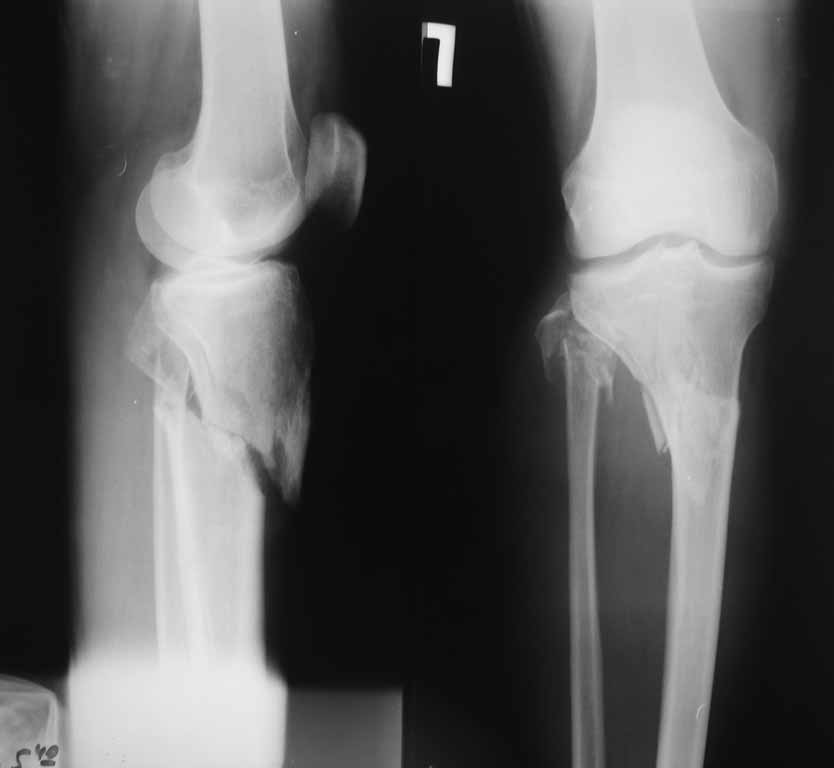

Двухколоннный перелом тибиал плато с вовлечением проксимального диафиза. Внутрисуставной компонент без смещения, и такой перелом можно лечить любым из описанных методов, о которых говорят наши коллеги.

Удобно аппаратом Илизарова или интрамедуллярным гвоздем. Гвозди не так сложно, как пугают, тем более Александр готов помощь с методичкой. Сперва надо установить компрессирующие шурупы на мыщелки. Давно отказались в пользу 3.5-4.0 мм кортикальных вместо толстых спонгиозных, потому что не доказаны преимущества толстых шурупов. Тонкие шурупы в субхондральной зоне смотрятся намного элегантнее, чем толстые 6.5.

Это мероприятие превращает перелом в простой диафизарный, который легко можно фиксировать гвоздем. Шурупы надо установить сзади предполагаемого места введения гвоздя.

Как понял, аппарат Илизарова не рассматривается предпочтительным для фиксации методом, хотя на фоне отека было бы идеальным для данного перелома. Для пластины требуется идеальная кожа, иначе наличие “суперсовременных имплантов” не поможет, и могут развиться серьезные осложнения.

Частая ошибка, когда фиксацию двух колонного перелома проводят одиночной пластиной, т.е с одной стороны, и такая фиксация не удерживает, происходит вторичноое смещение. Необходимо нейтрализовать второй пластиной или дополнительным наружным фиксатором.

Кстати, коллеги правы для уточнения характера перелома надо делать Компьютерную Томографию.